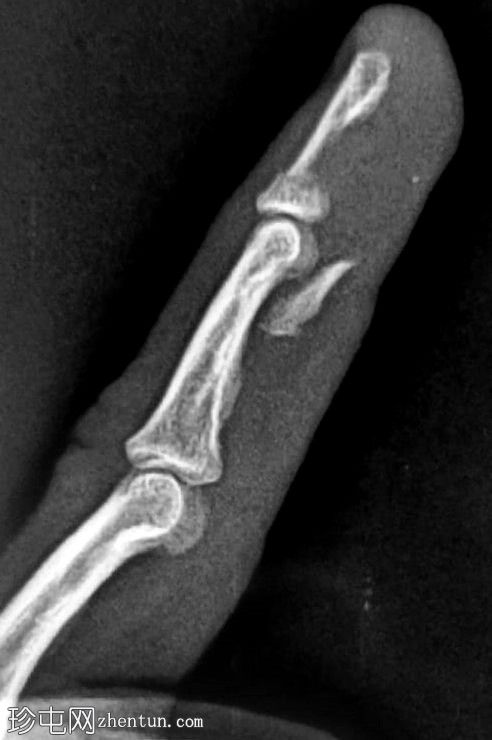

这是无名指侧位X光片。远端指骨掌侧骨性撕脱,位于中节指骨头和远端指骨干水平。远端指骨关节外骨折延伸至靠近其基底部的背侧皮质。无脱位/骨损伤。